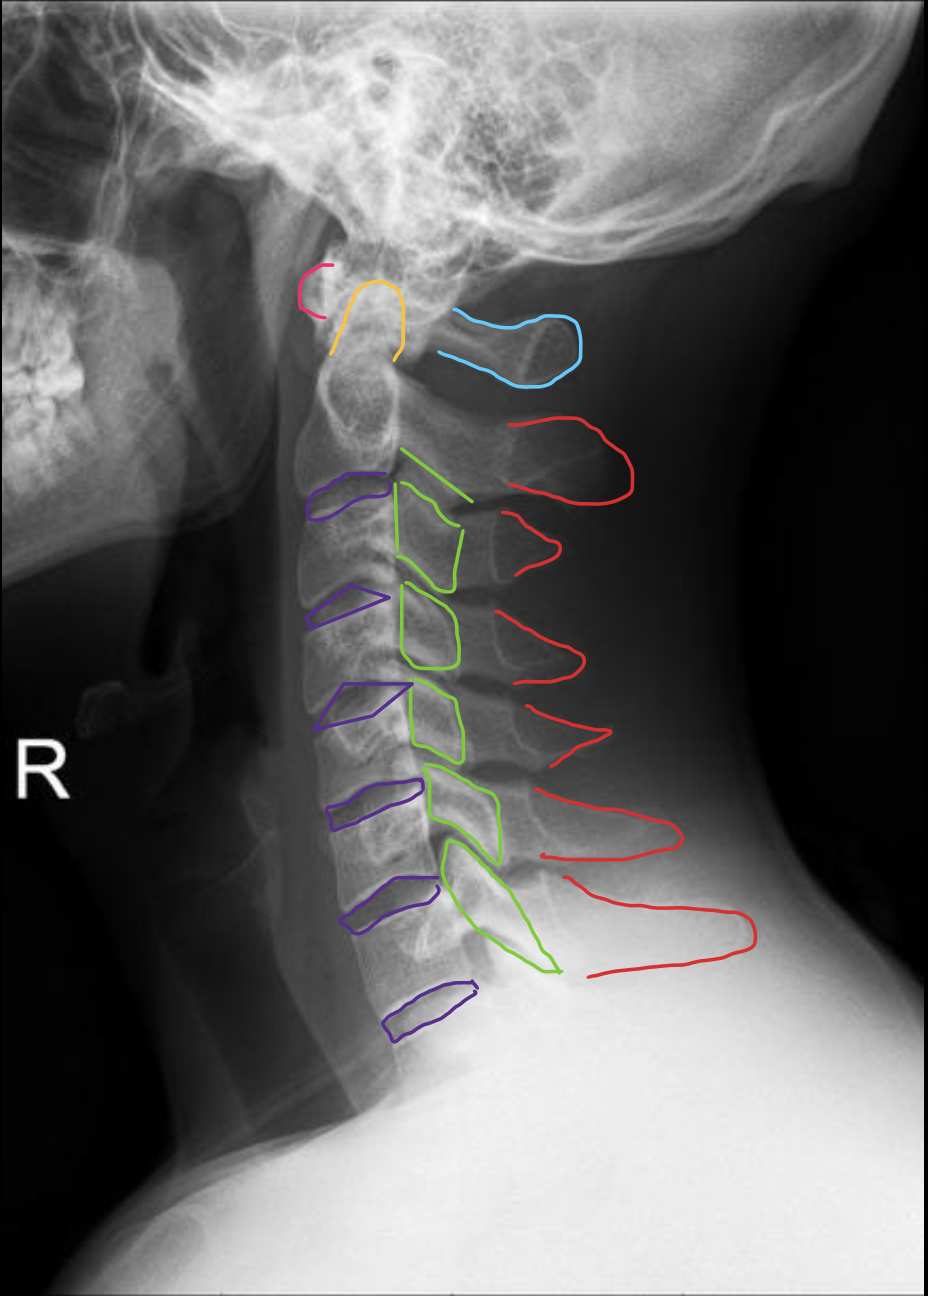

C2

C3

C4

c5

c6

c7

T1

1ST Rib

钩突

Uncinate process

关节柱 / 侧块

Articular pillars

棘突

Spinous process

乳突气房

Mastoid air cells

下颌角

Angle of mandible

椎间隙(Intervertebral Disc space)

IVD space

气管

Trachea

齿状突

Odontoid process C1

颅底

Base of skull

下颌骨

Mandible